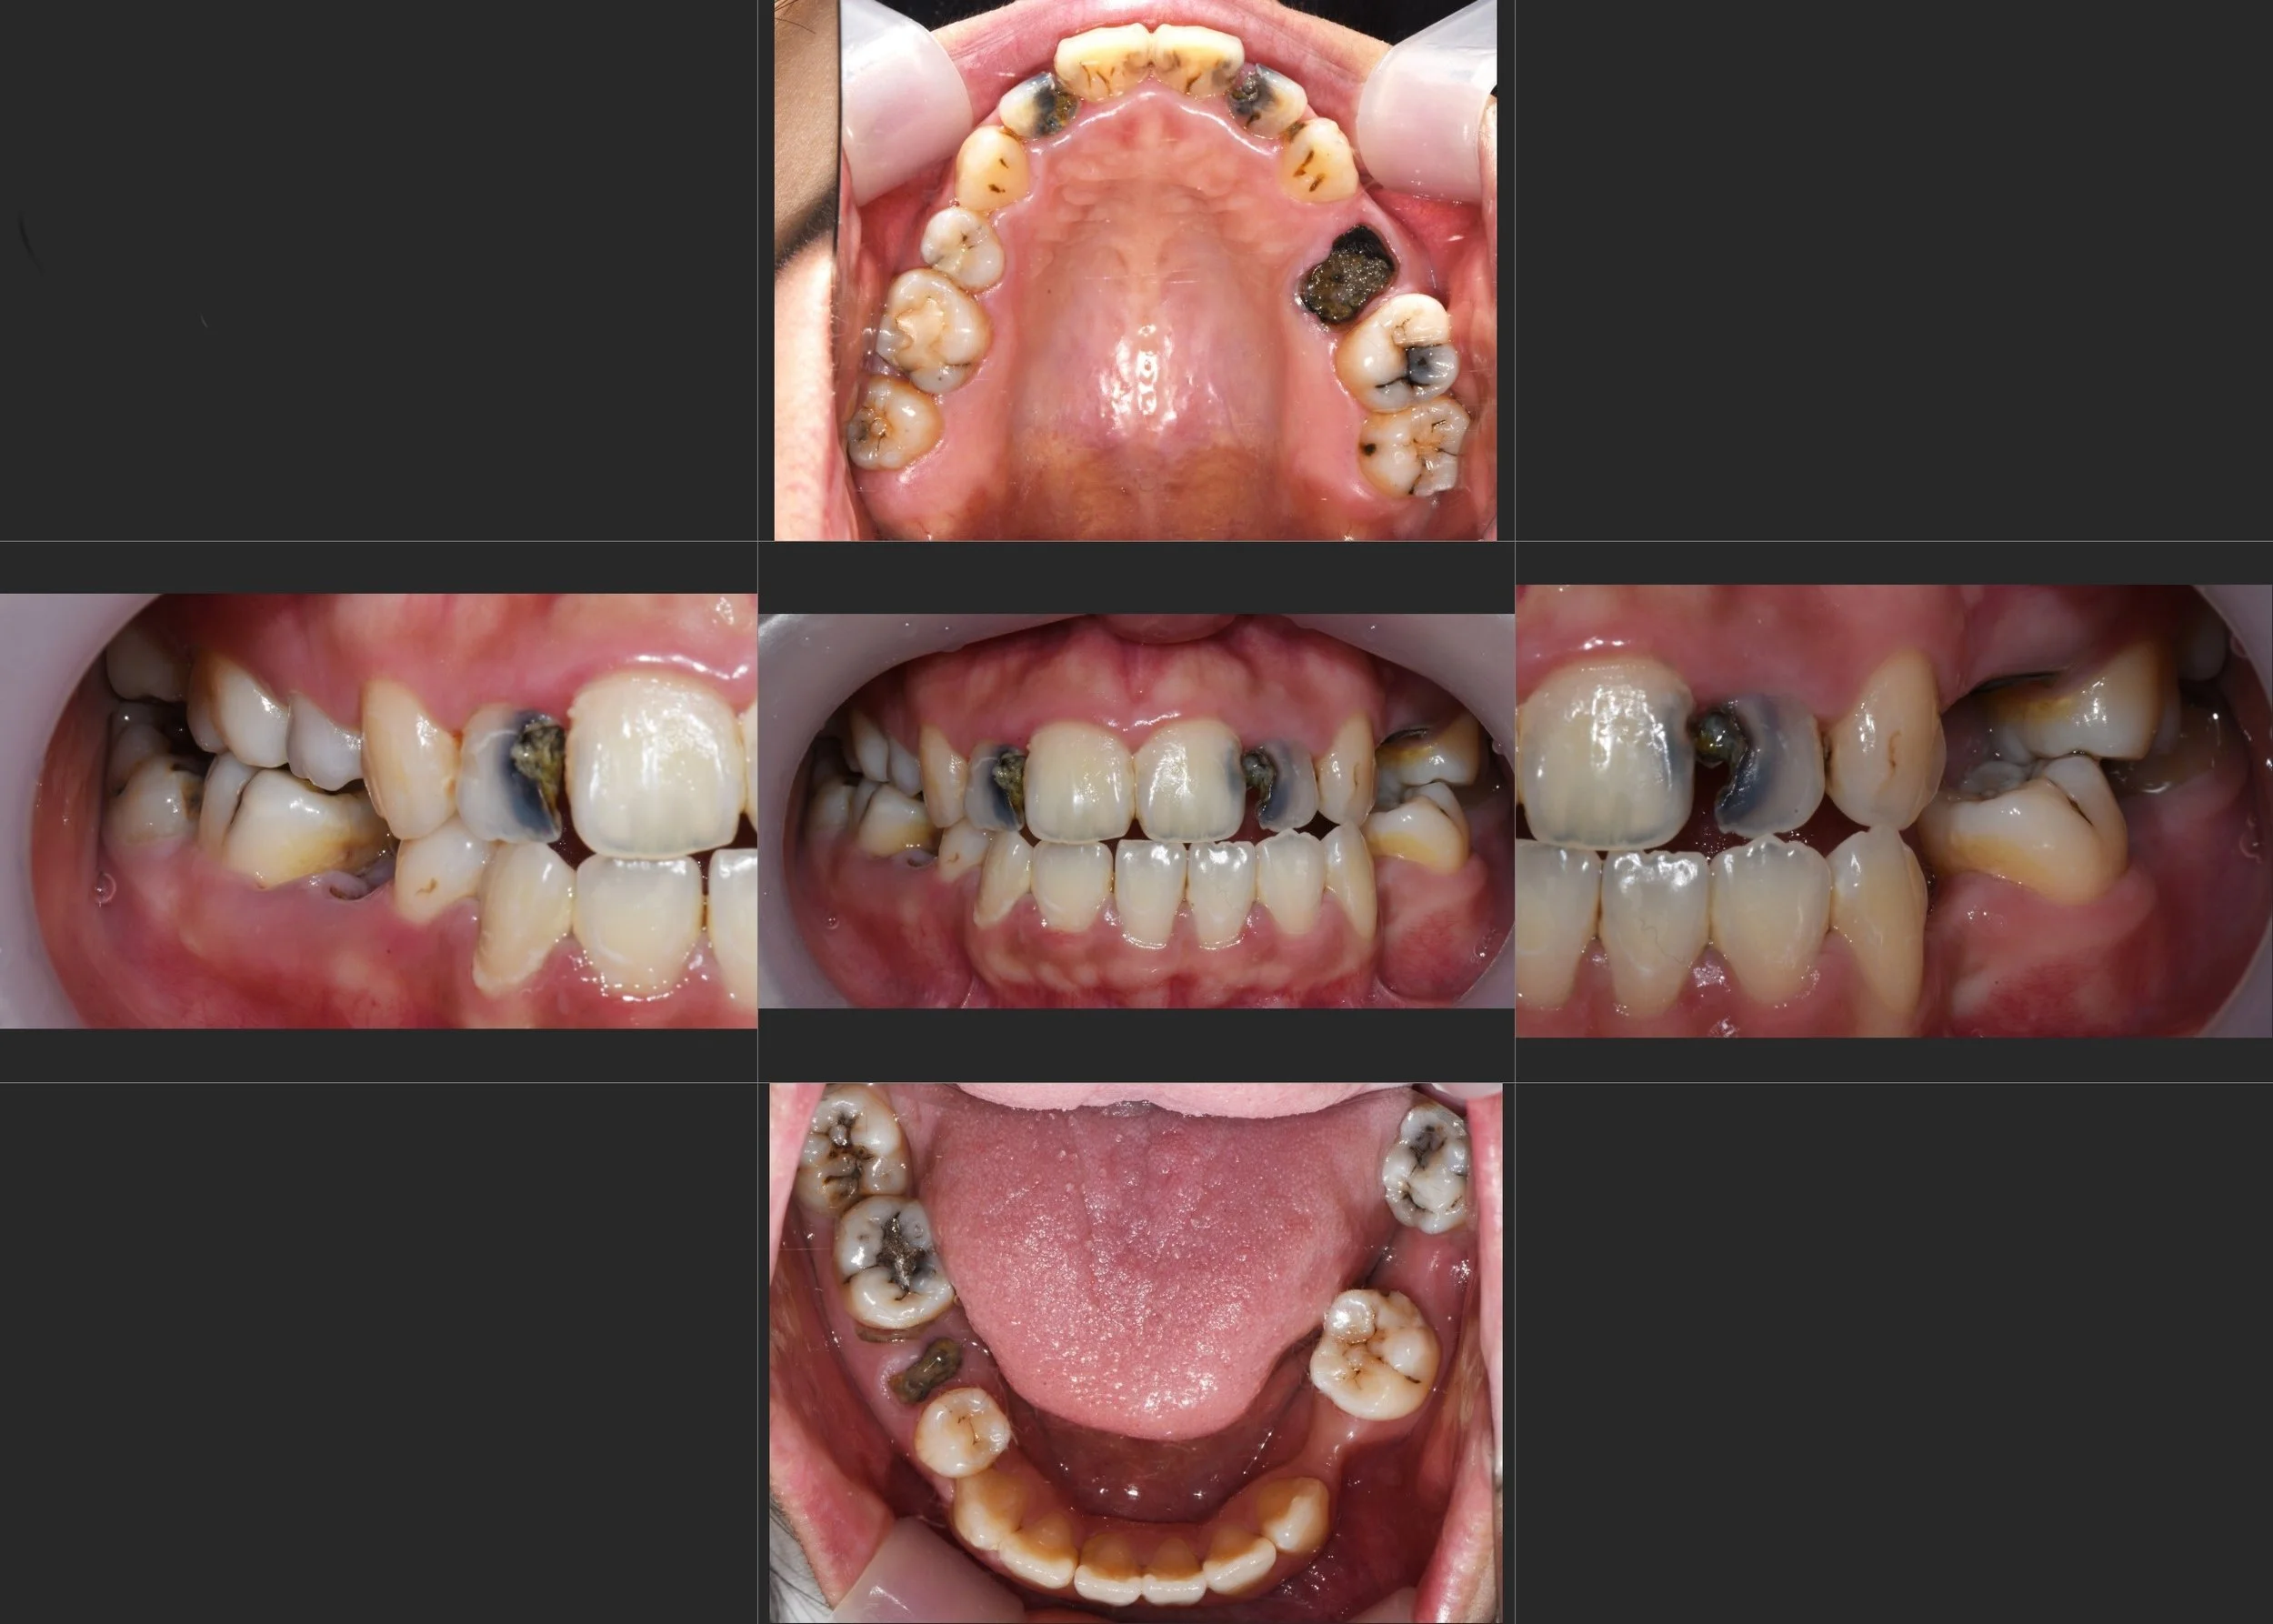

35. Comprehensive Full-Arch Transformation: Restoring Confidence in a Young Phobic Patient

Reversing the effects of generalized rampant caries and occlusal collapse in a female patient in her 20s. A tooth-preserving, implant-assisted approach focused on stable VDO elevation and overcoming social anxiety.